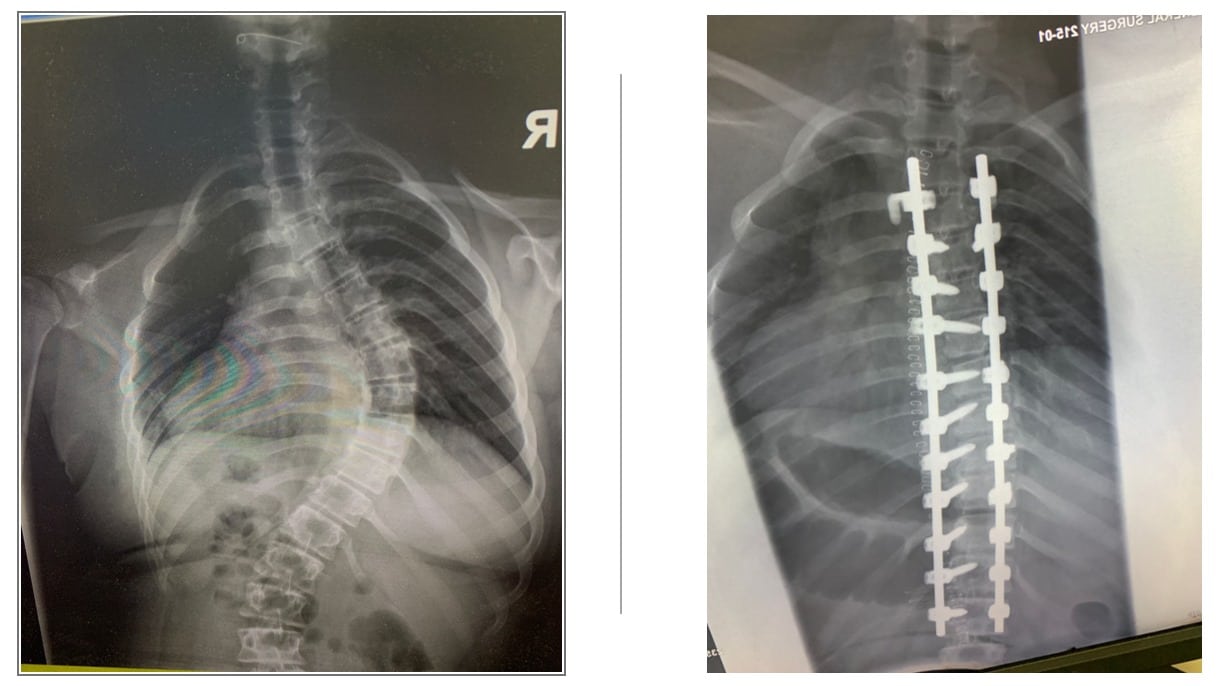

إجراء عملية تصحيح عمود فقري لأول مرة في مستشفى السلط الجديد